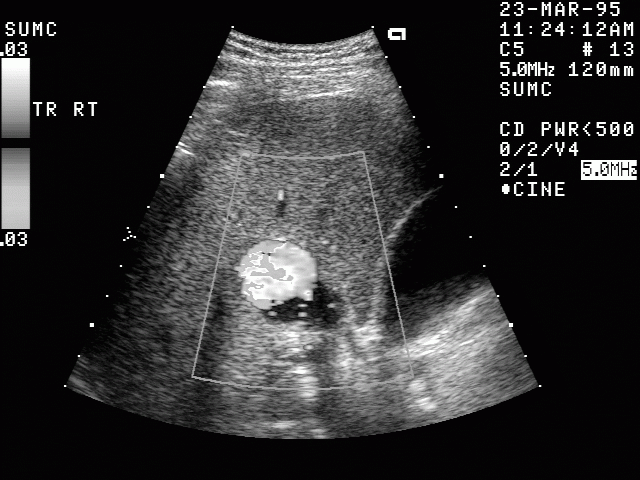

Ultraschallbild eines Leberhämangioms - Sonographie

Besondere Bedeutung hat die Dopplersonographie erlangt. Mit dem Dopplerprinzip kann die Fließgeschwindigkeit und -richtung von Blut dargestellt werden, um Gefäßverengungen und -verschlüsse nachzuweisen oder stark durchblutete Tumore zu erkennen.